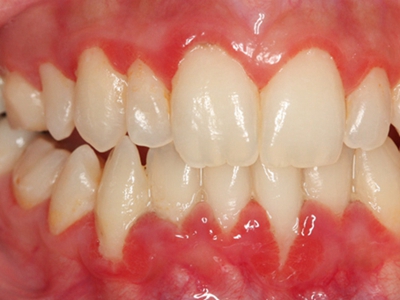

牙龈炎是发生于牙龈组织的炎症,患者可出现牙龈出血伴肿胀、发红、正常形态改变和偶尔不适等症状。本病主要由口腔卫生状况差导致,包括口腔不洁、牙菌斑等,诊断依据临床检查,治疗包括专业牙齿清洁和加强家庭口腔卫生。

牙龈炎可先引起牙齿与牙龈之间的沟(龈沟)加深,然后牙龈充血,炎症围绕一个或多个牙齿,伴牙龈乳头肿胀和易出血。一般无痛,可自行消退,也可维持轻度炎症数年。